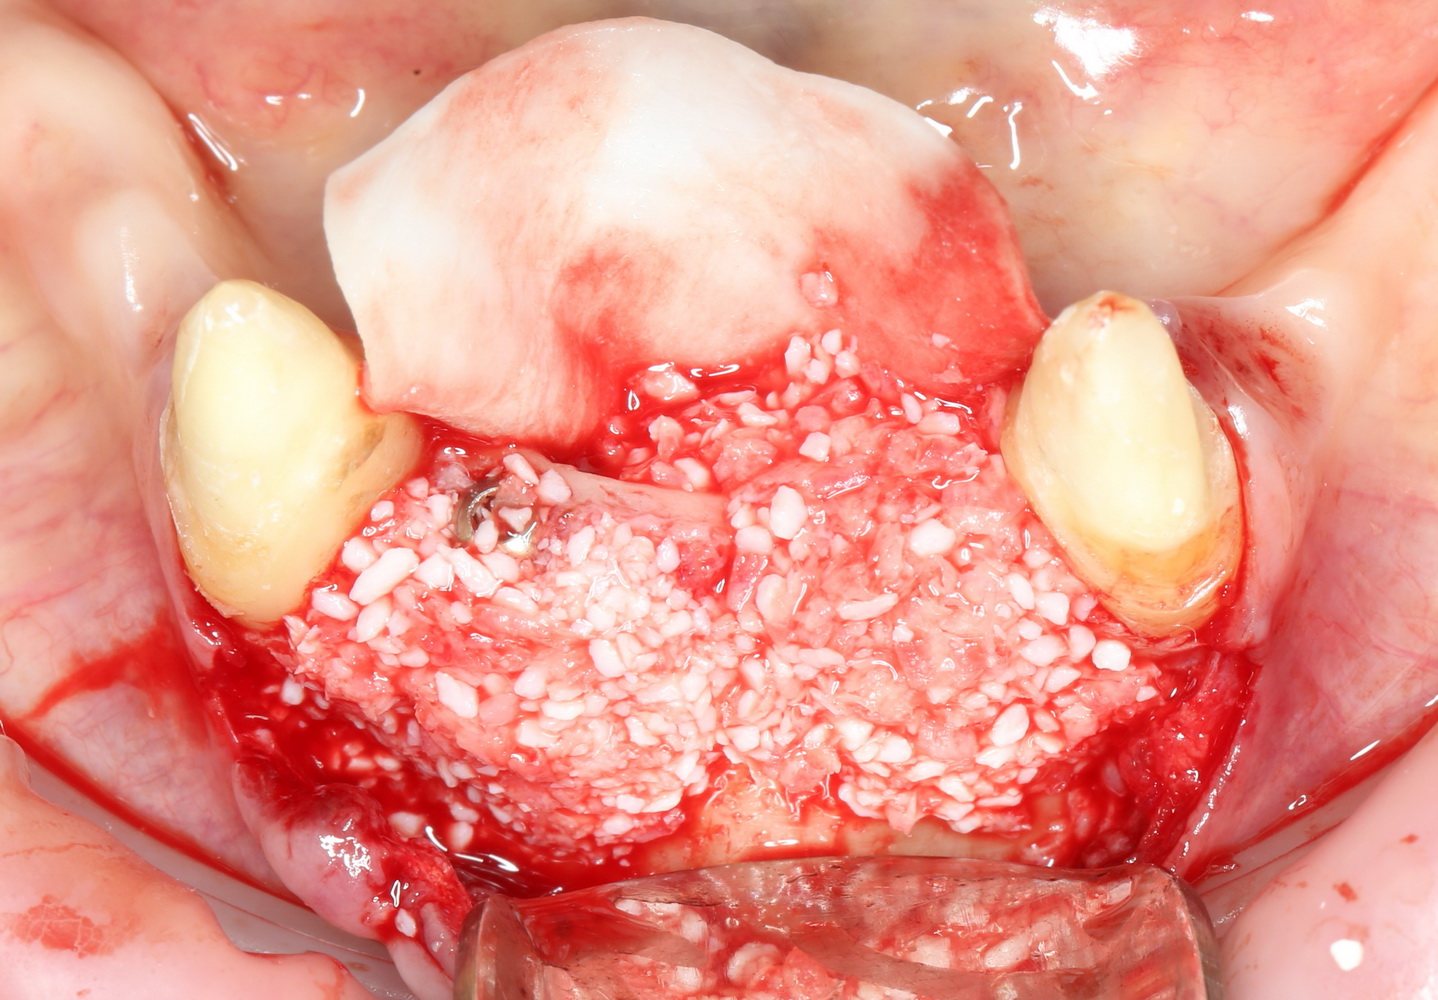

сделать остеопластику там, где это требовалось:

расставить импланты, по шесть штук на каждую челюсть. Разумеется, не все сразу, а постепенно: